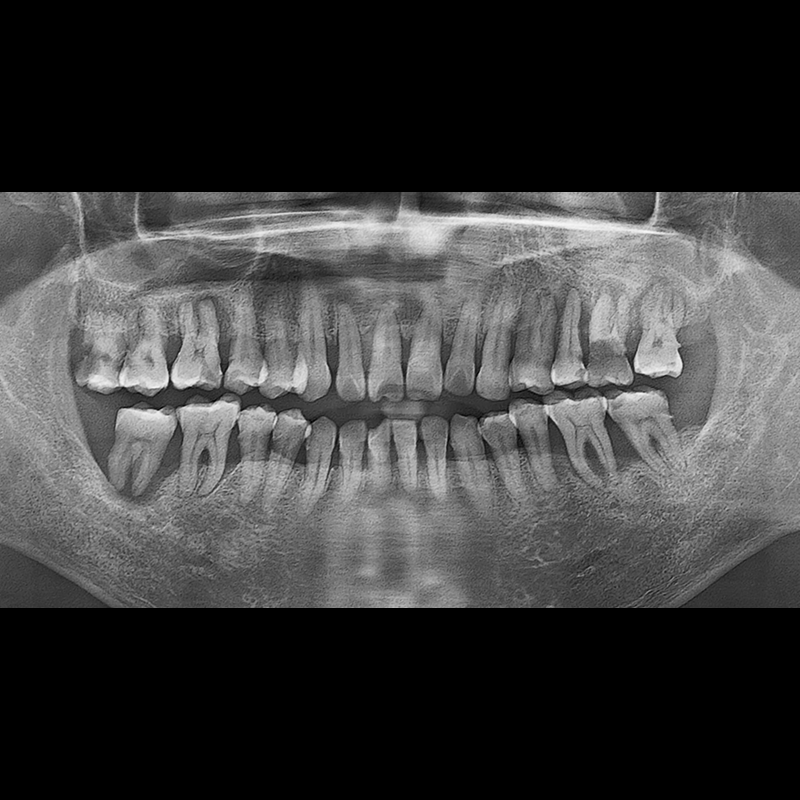

BEFORE AFTER

インプラント手術事例 2025.05.30

欠損した歯の部分と、生かしにくい歯の位置にインプラントを植立しました。